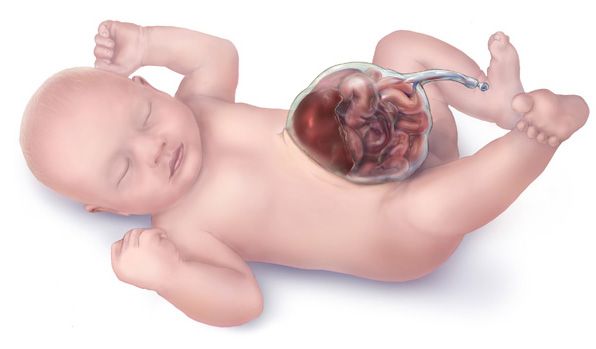

Омфалоцеле (Omphalocele) — это врождённый дефект брюшной стенки, при котором органы брюшной полости (кишечник, печень и др.) выходят за пределы живота через пупок. Как правило, вышедшие органы покрыты тонкой, почти прозрачной оболочкой, но иногда она может быть разорвана.

Синонимы: экзомфалос, грыжа пупочного канатика.

Омфалоцеле видно сразу при рождении: в месте пуповины определяются органы или части органов покрытые оболочкой (грыжевым мешком). Она может быть тонкой и полупрозрачной или более плотной, почти волокнистой из-за внутриутробного воздействия амниотической жидкости.

Иногда оболочка может быть разорвана. В таком случае она будет лишь частично покрывать органы. Разрыв может произойти внутриутробно или во время родов. Если это случилось внутриутробно, то после родов вышедший наружу кишечник может быть покрыт густым спутанным экссудатом.

Также у новорождённого могут отмечаться признаки дыхательной и сердечно-сосудистой недостаточности (одышка, синюшность кожи, учащённое сердцебиение), при этом ребёнок не кричит и не плачет или кричит слабо. Иногда снижен мышечный тонус и определяются дефекты развития других органов, например заячья губа.

В тяжёлых случаях ткани и органы, вышедшие наружу, могут иметь чёрно-коричневую окраску, это значит, что начался их некроз (омертвение).